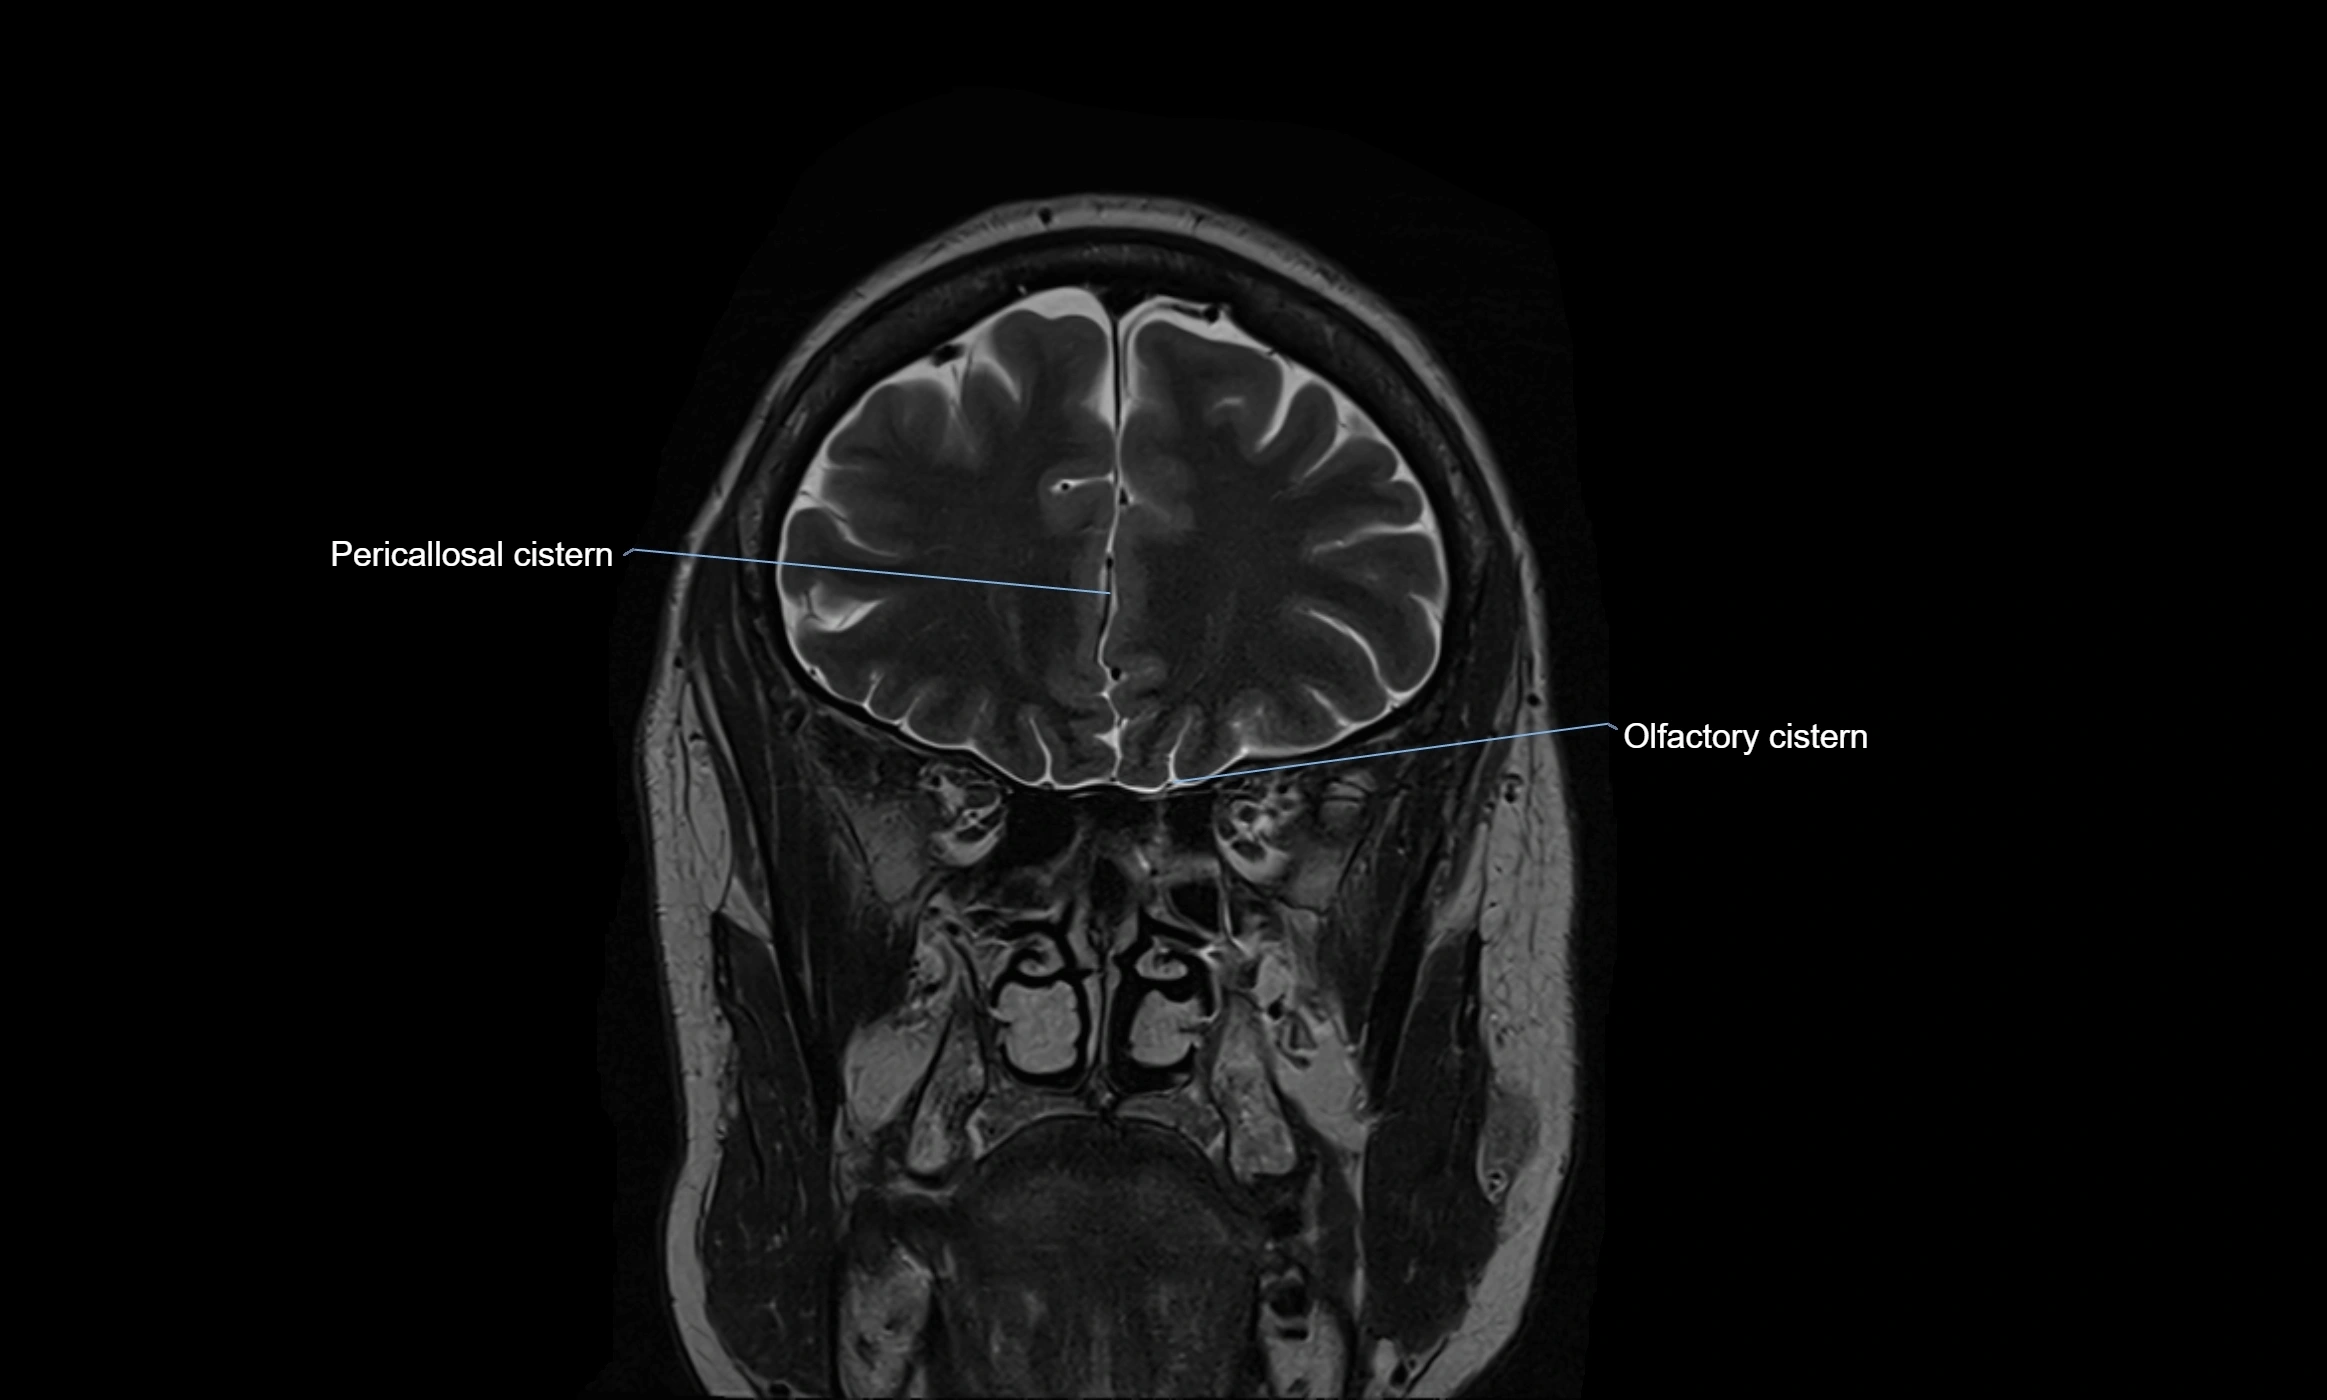

MRI images

image